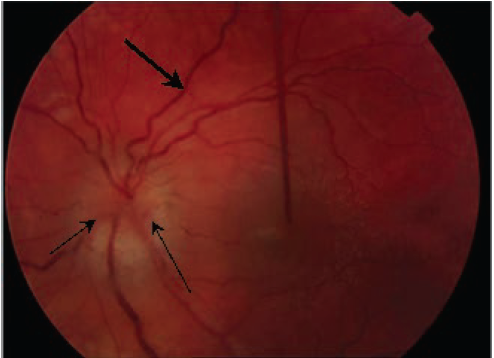

Infectious diseases

Sanjeev Y. Tuli, MD; Sharda Udassi, MD; Jaclyn Otero, MD; Jai P. Udassi, MD

An 8-year-old girl presented to a hospital pediatrics department with a 3-month history of recurrent fever; a self-resolving, truncal, evanescent, macular rash; bilateral leg pain; and 1-day history of what...